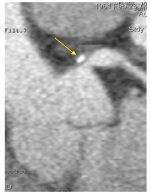

Peu invasif mais irradiant (irradiation peu différente de celle d’une coronarographie actuellement), il assure le diagnostic des sténoses des artères coronaires de plus de 1,5 mm de diamètre (figure 40.5) ainsi que les diagnostics différentiels. De plus, il permet de mettre en évidence la présence de lésions athéromateuses coronaires même si elles ne sont pas à l’origine de sténose > 50 %.

Fig. 40.5. Angioscanner coronaire montrant une sténose de l’artère coronaire gauche en rapport avec une plaque athéromateuse (flèche).

Source : CERF, CNEBMN, 2022.